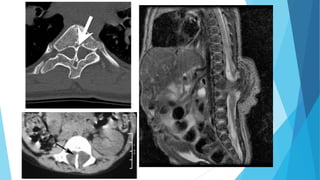

Fig. 9: TC columna a. Anomalía constitucional del arco posterior de L5 con

espina bífida oculta (flecha azul) y lisis ítsmica izquierda. (flecha roja). b.

Espina bífida de C7 (flecha verde). c. Reconstrucciones en 3D. Espina bífida de

C1

RMN. A, B. Sagital SE T1.Terminación del cono medular (flecha) por detrás de S1 en un

lipoma (*).B. Sagital SE T1. Espina bífida oculta en S3 (flecha).